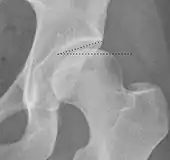

| Caput-sourcil angle[21] | ![]() |

Superior to the Tönnis angle in cases without joint space narrowing or subluxation.[21] The medial point of the sourcil is at the same height as the most superior point of caput femoris. | −6 to 12°[21]

|